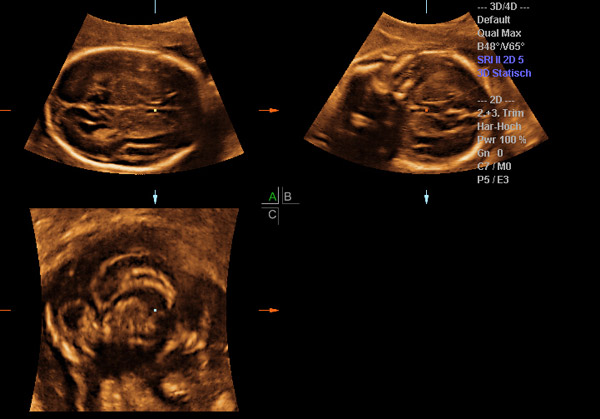

Die Möglichkeit, Ultraschallaufnahmen dreidimensional zu speichern, wird als 3D Technik bezeichnet. Dank sehr schneller Verrechnung dieser Bilder ist es möglich diese Bilder annähernd in Echtzeit wiederzugeben. Dann spricht man von 4D- Aufnahmen. Dieses Werkzeug nutzt der Pränataldiagnostiker, um Organe genauer untersuchen zu können (z. B. Gehirn). Wie bei einer Kernspinnuntersuchung können dreidimensionale Volumenblöcke gespeichert werden, die dann in der Nachschau beliebig gedreht und geschnitten werden können. In der Hand des Geübten ein großer diagnostischer Gewinn. Natürlich können auch Oberflächen (z.B. Gesicht) betrachtet werden, dies stellt jedoch nur einen kleinen Anteil an Möglichkeiten der 3D Technik dar.